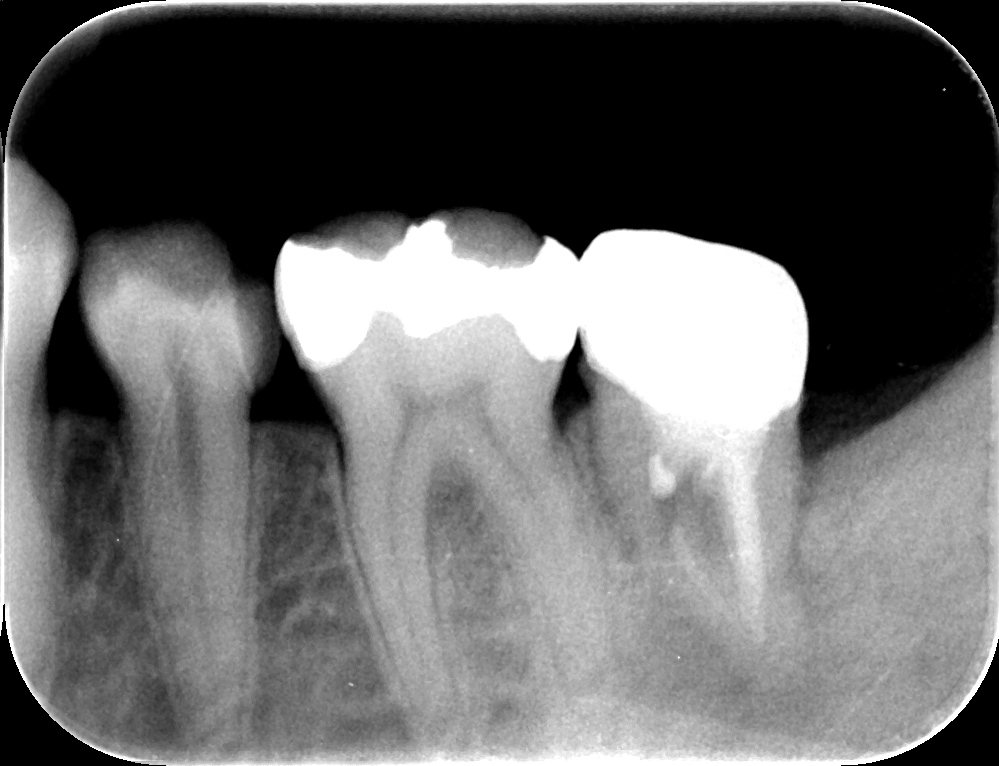

コーヌスデンチャーとは残っている歯に冠のような金属を被せてその上にさらに金属を被せる

2重の冠でできた入れ歯になります。茶筒の原理で固定されるため安定感が高く、審美性や装着感に

優れています。ドイツで開発されたテレスコープデンチャーの一種です。

画像の様なイメージになります。針金を使いませんので

見た目がよくまた維持力も大きくとても良好な義歯となります。